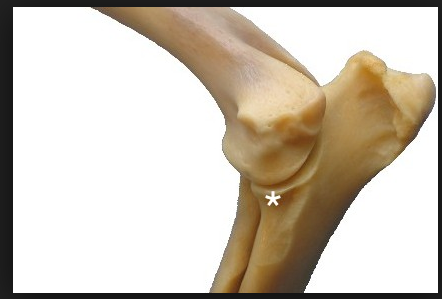

Blue arrow- supratrochlear foramen

Red arrow- medial epicondyle of the humerus

red and blue arrow

what is the third joint that makes up the elbow?

red- humeroradial joint

blue arrow- humeroulnar joint

third joint- radioulnar joint